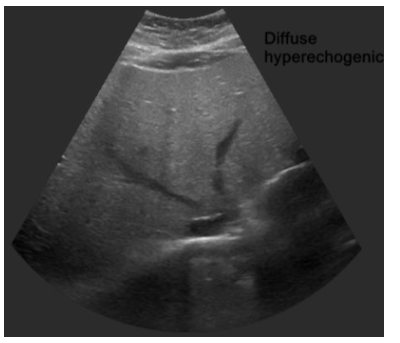

간초음파 사진의 diffusely increased echogenicity는 지방간 소견입니다.정상 hepatic vein의 wall은 liver parenchyme보다 hyperechoic하지만 사진의 hepatic vein wall은 isoechoic하며 parenchyme의 echogenicity가 증가되어 있음을 알 수 있습니다.

Fatty liver 초음파 소견

① 정상 hepatic vein의 wall은 liver parenchyme보다 hyperechoic하지만 지방간에서는 isoechoic합니다 (아래 첫 번째 사진과 세 번째 사진 비교)